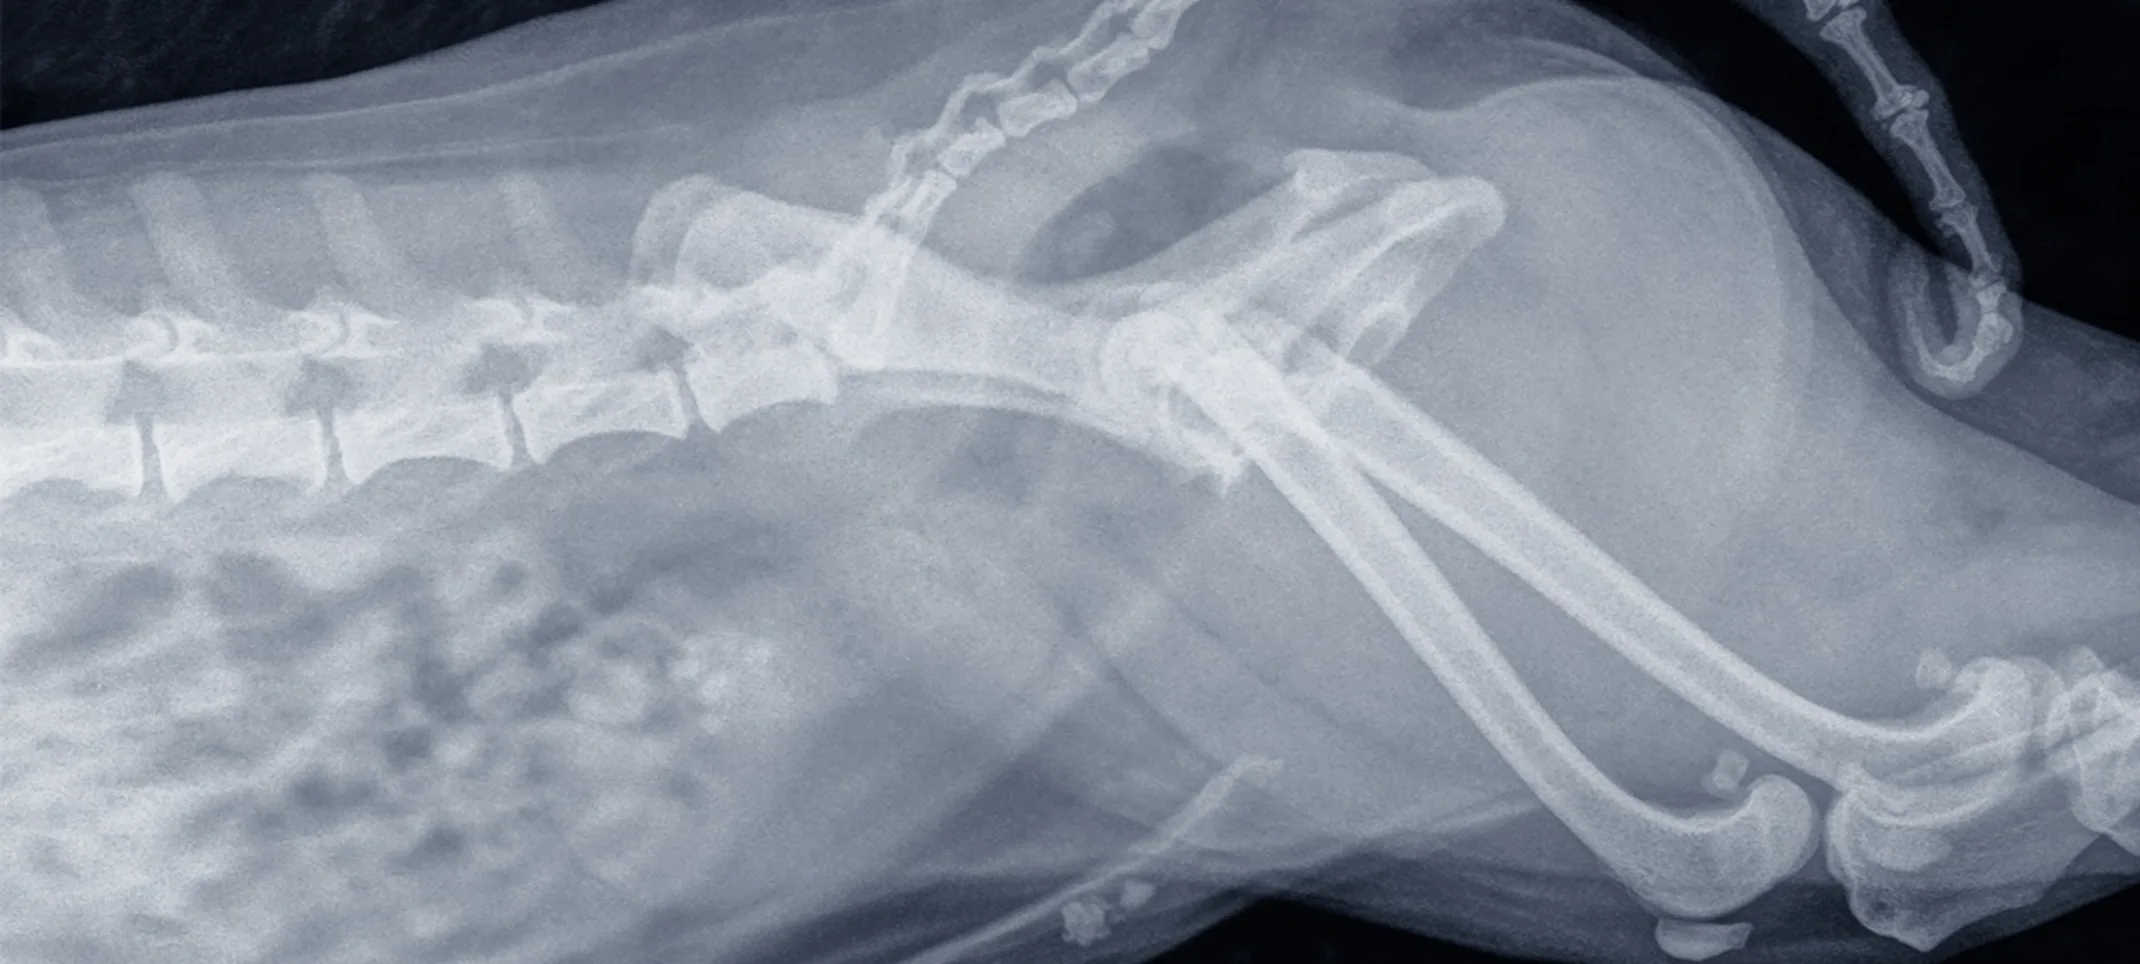

We’re equipped to perform routine radiography services to identify many types of illness or injury when pets are sick or suffer a trauma.

Radiography, also known as X-rays, is one of the most common and valuable medical diagnostic tools. X-rays are highly useful for screening areas of the body that have contrasting tissue densities, or when evaluating solid tissues.

If your pet is sick or has suffered a trauma, X-rays provide a minimally invasive tool to help our doctors diagnose your pet. X-rays are also used in general wellness exams to diagnose potential problems before they become serious.

We may recommend veterinary X-rays as part of a diagnostic procedure if your pet is experiencing any health conditions or as a preventive measure in a routine senior wellness examination. We use radiology alone or in conjunction with other diagnostic tools depending on the patient’s condition. We’re fully equipped to perform routine radiology services to identify many types of illness or injury when pets are sick or suffer a trauma.

X-rays can be used to detect a variety of ailments in animals including arthritis, tumors, bladder and kidney stones, and lung abnormalities such as pneumonia. They are also used to evaluate bone damage, the gastrointestinal tract, respiratory tract, genitourinary system, organ integrity, and even identify foreign objects that may have been ingested. Dental radiographs help distinguish healthy teeth from those that may need to be extracted, and identify any abnormalities beneath the gums including root damage, tumors, and abscesses. In some cases, we may need to sedate your pet or use short-acting general anesthesia.